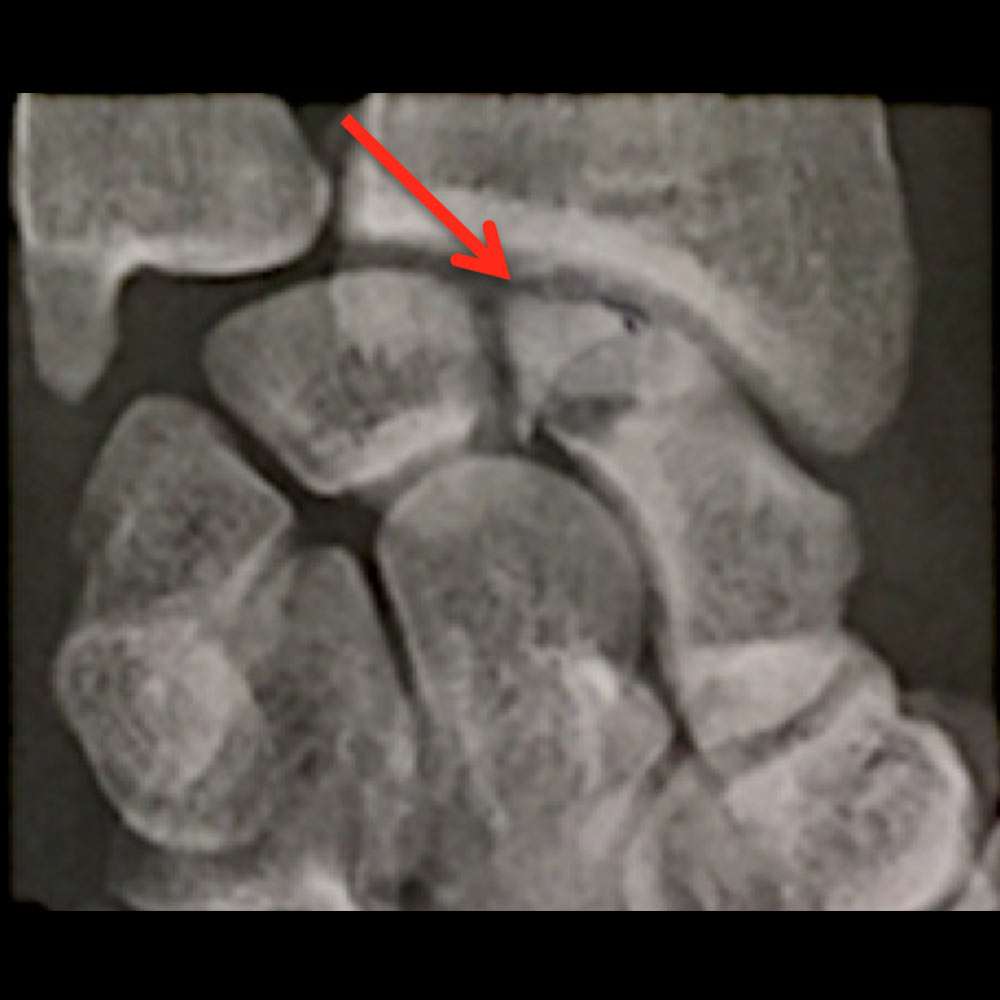

Scanner du poignet gauche montrant une fracture du pole proximal du scaphoïde avec nécrose de celui-ci (flèche rouge) chez un jeune homme de 25 ans

IRM du poignet gauche montrant une fracture du pole proximal du scaphoïde avec nécrose de celui-ci (flèche rouge) chez un jeune homme de 25 ans

Radiographie du poignet gauche montrant une fracture du pole proximal du scaphoïde avec nécrose de celui-ci (flèche rouge) chez un jeune homme de 25 ans